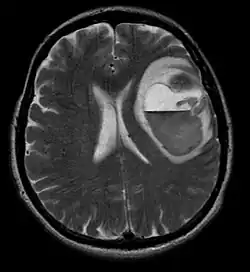

Na -MRI ukazuje intrakraniální tumor jako masivní lézi, která se po použití kontrastní látky může stát více luminiscenční. Vždy však dojde k anomálii signálu -Magnetická rezonance, která indikuje přítomnost neoplazie nebo vazogenního edému. Obvykle zvýšená luminiscence (zesílení kontrastu) svědčí pro nádor vyššího stupně malignity. Pro glioblastom je charakteristický kontrastní prstenec, jehož luminiscenční část odpovídá vitální části maligního nádoru a tmavší -hypointense oblast odpovídající nekróze tkáně.

Glioblastomy

Nejčastějšími a maligními nádory z gliových buněk jsou glioblastomy. Skládají se z heterogenní masy špatně diferencovaných buněk astrocytomu hlavně u dospělých. Obvykle se vyskytují v mozkových hemisférách, vzácněji v mozkovém kmeni nebo míše. Kromě velmi vzácných případů, jako všechny mozkové nádory, nepřesahují struktury centrálního nervového systému.

Glioblastom může vzniknout z difuzního (II. stupně) nebo anaplastický astrocytom (III. stupeň) rozvíjet. V druhém případě se nazývá sekundární. Pokud se však objeví bez předchozího zhoubného nádoru nebo důkazu o předchozím zhoubném bujení, označuje se jako primární. Glioblastomy se léčí chirurgicky, ozařováním a chemoterapií. Jsou obtížně léčitelné a jen málo případů přežívá déle než tři roky.